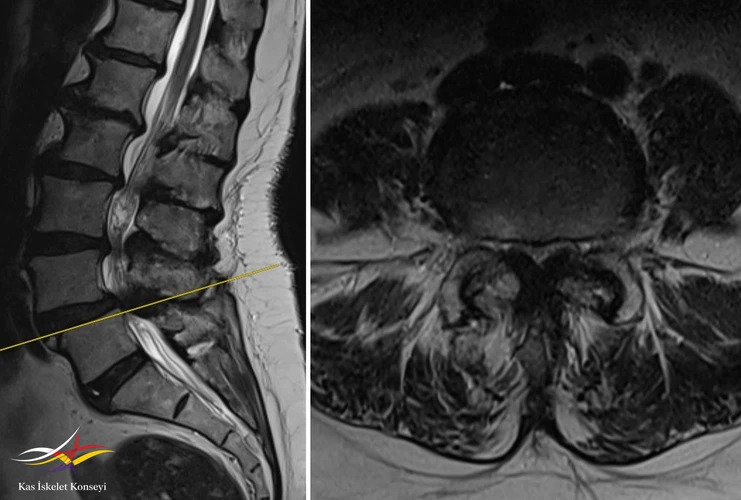

Resim 1. 2029 yılına ait suboptimal MRG de L4-5 listezis ve dar kanal görülmekte.

Resim 5. L4-5 seviyesinde dejeneratif listezis ve belirgin kanal darlığı görülmekte.